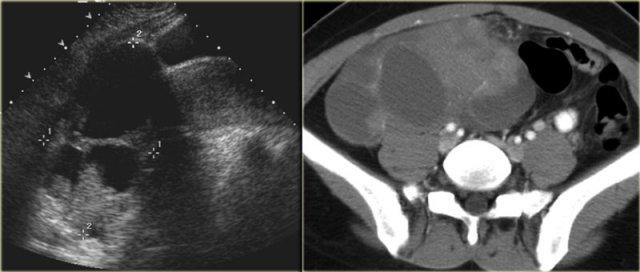

Trường hợp tiếp theo là siêu âm qua thành bụng cho thấy một khối nang đa thùy bên trái.

Hình ảnh này gợi ý u nang tân sinh buồng trứng nhưng không xác định được buồng trứng.

CT trên cùng bệnh nhân cho thấy một khối nang đa thùy tiếp giáp bàng quang, có liên quan đến tĩnh mạch buồng trứng trái (mũi tên).

Có các vách ngăn dày và thành dày không đều.

Dựa trên hình ảnh CT này, không thể phân biệt giữa tổn thương buồng trứng lành tính như u nang tuyến xơ và tổn thương buồng trứng ác tính.

Tổn thương được phẫu thuật cắt bỏ và kết quả giải phẫu bệnh xác định là u nang tuyến xơ.

Siêu âm cho thấy một tổn thương nang đa thùy kích thước rất lớn ở vùng phần phụ phải.

Một số thùy không có âm vang. Các thùy khác chứa âm vang mức độ thấp đồng nhất, phù hợp với thành phần giàu protein như xuất huyết hoặc trong trường hợp này là chất nhầy. Các vách ngăn mỏng, ngoại trừ các vách phía sau có vẻ dày hơn một phần do độ phân giải hình ảnh thấp hơn ở độ sâu lớn. Các vách ngăn không có mạch máu. Không có thành phần đặc. Không có cổ trướng.

Mặc dù không có thành phần đặc và không có mạch máu trên siêu âm Doppler màu, kích thước lớn và hình thái đa thùy của tổn thương này vẫn nghi ngờ cho một u nang buồng trứng thực sự và cần được đánh giá thêm.

CT có tiêm thuốc cản quang cho thấy các đặc điểm tương tự. Các thùy có tỷ trọng khác nhau, phù hợp với hàm lượng protein khác nhau.

Không có cổ trướng, không có tổn thương cấy ghép phúc mạc và không có hạch bạch huyết to.

Kết quả giải phẫu bệnh xác định đây là ung thư biểu mô tuyến nang nhầy có tiềm năng ác tính thấp.

Các vách ngăn mỏng, tương đối ít mạch máu, không có thành phần đặc rõ ràng, không có cổ trướng và ung thư biểu mô phúc mạc, cũng như không có xâm lấn, gợi ý một tổn thương có tiềm năng ác tính thấp (LMP).

Tuy nhiên, cần lưu ý rằng chẩn đoán này không thể được xác lập chỉ dựa trên các đặc điểm hình ảnh đơn thuần.

Đặc biệt, sự vắng mặt của xâm lấn vào mô đệm buồng trứng không thể được đánh giá một cách đáng tin cậy trên hình ảnh.